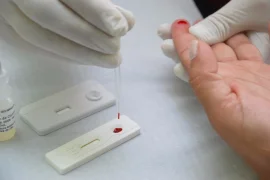

Pesquisadores desenvolvem Teste Popular de COVID-19 que amplia acesso ao diagnóstico

Dezembro Vermelho realiza mais de 600 testes para HIV na P1 de Pirajuí

Governo de SP inicia testagem para Covid-19 na rede estadual de ensino